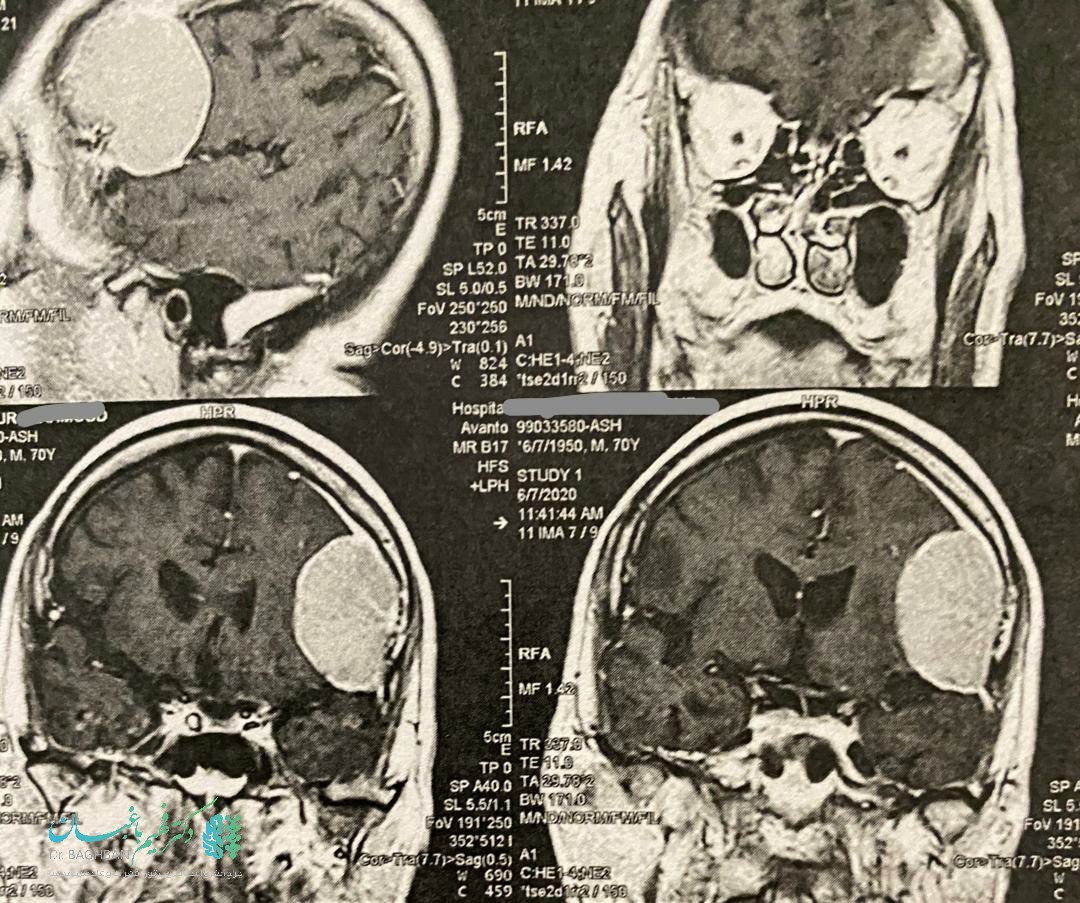

بیمار آقای ۷۸ ساله که با تغییرات رفتاری مراجعه نمودند. با تشخیص تومور مننژیوما توسط دکتر فهیم باغبان مورد جراحی قرار گرفتند :

تصاویر قبل از عمل

قبل از عمل تومور